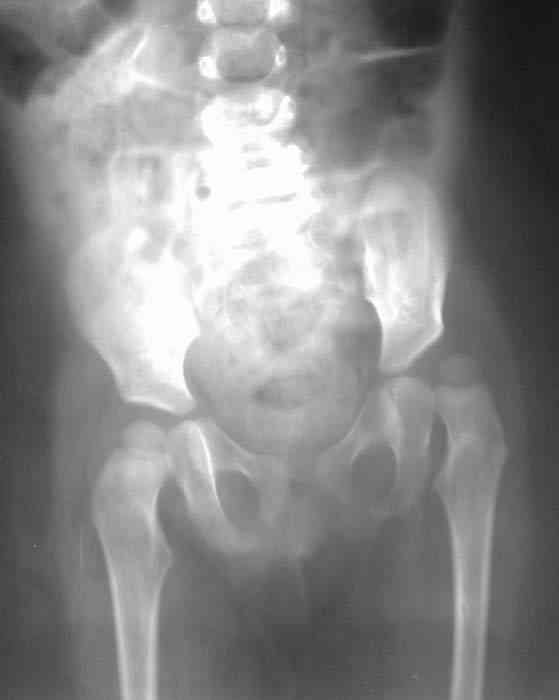

Уважаемые коллеги!Окажите, пожалуйста, консультативную помощь! Девочка, 1 г 9 мДЗ: врожденная патология головного мозга, врожденная дисплазия, подвывих, приводящая контрактура левого тазобедренного сустава, микроцефалия, миоклонические припадки, грубая задержка психофизического развития, с-м Айкарди?

Жалобы родителей на укорочение левой ноги, невозможность ходить, сидеть. Впервые обратили внимание на укорочение левой нижней конечности 4 месяца назад. Осмотрена по месту жительства в ЦРБ, направлена в ДНИИТО. Ребенок от I беременности, I срочных родов, протекавших с анемией, осложненные преждевременным отхождением вод, вес при рождении 4100. В анамнезе - пупочная грыжа, респираторные заболевания, рахит, тетрапарез, судорожный синдром, сальмонельоз.

12.06.05. МРТ головного мозга/консультация невролога - микроцефалия со структурной аномалией головного мозга (агенезия мозолистого тела, атрезия передних рогов боковых желудочков, расширение затылочных швов с обеих сторон), задержка психомоторного развития, тетрапарез, миокинетические, эпилептические приступы, частичная атрофия зрительных нервов.

Особенности объективного осмотра в настоящее время:Умеренный тетрапарез. Признаки рахита (деформация костей черепа, четки). Дыхание пуэрильное. Тоны сердца ритмичные, шумов нет. Живот мягкий, безболезненный, печень +1,5 см. Склонность к запорам. Местный статус: резкое приведение левого бедра, относительное укорочение левой нижней конечности. Ограничение отведения в тазобедренных суставах, особенно слева. Гипертонус мышц левой нижней конечности. Ограничение сгибания в левом коленном суставе.

Объем движений (левый ТБС): сгибание-разгибание (фиксированное) 65-165; разведение - D 45, S 65. Положение сустава по отношению к линии Розера-Нелатона - D 0,5 см, S 1,5 см. Хронаксиметрия - возбудимость нервных стволов нижних конечностей в норме, двигательная реакция мышц типичная.